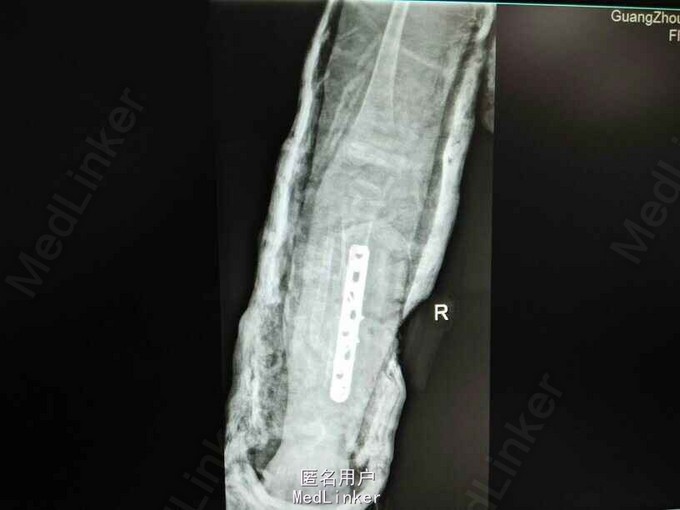

患女1岁8个月,患者母亲诉小孩出生时右小腿畸形,1岁时学走路跌倒后哭闹数天,小腿肿胀去医院检查示右胫腓骨折,稍做固定,1岁3个月时复查骨折未愈合,考虑先天性胫骨假关节,行手术治疗,现术后5个月复查未愈。目前小儿不能行走。

右下肢短缩约2cm,右小腿畸形,肌力检查不配合,

神经纤维瘤病,先天性胫骨假关节。该患者经过讨论及与家属多次沟通愈后情况,行病灶切除,取母体骨移植,AO锁定钢板内固定,暂时管型石膏外固定,并订制支具